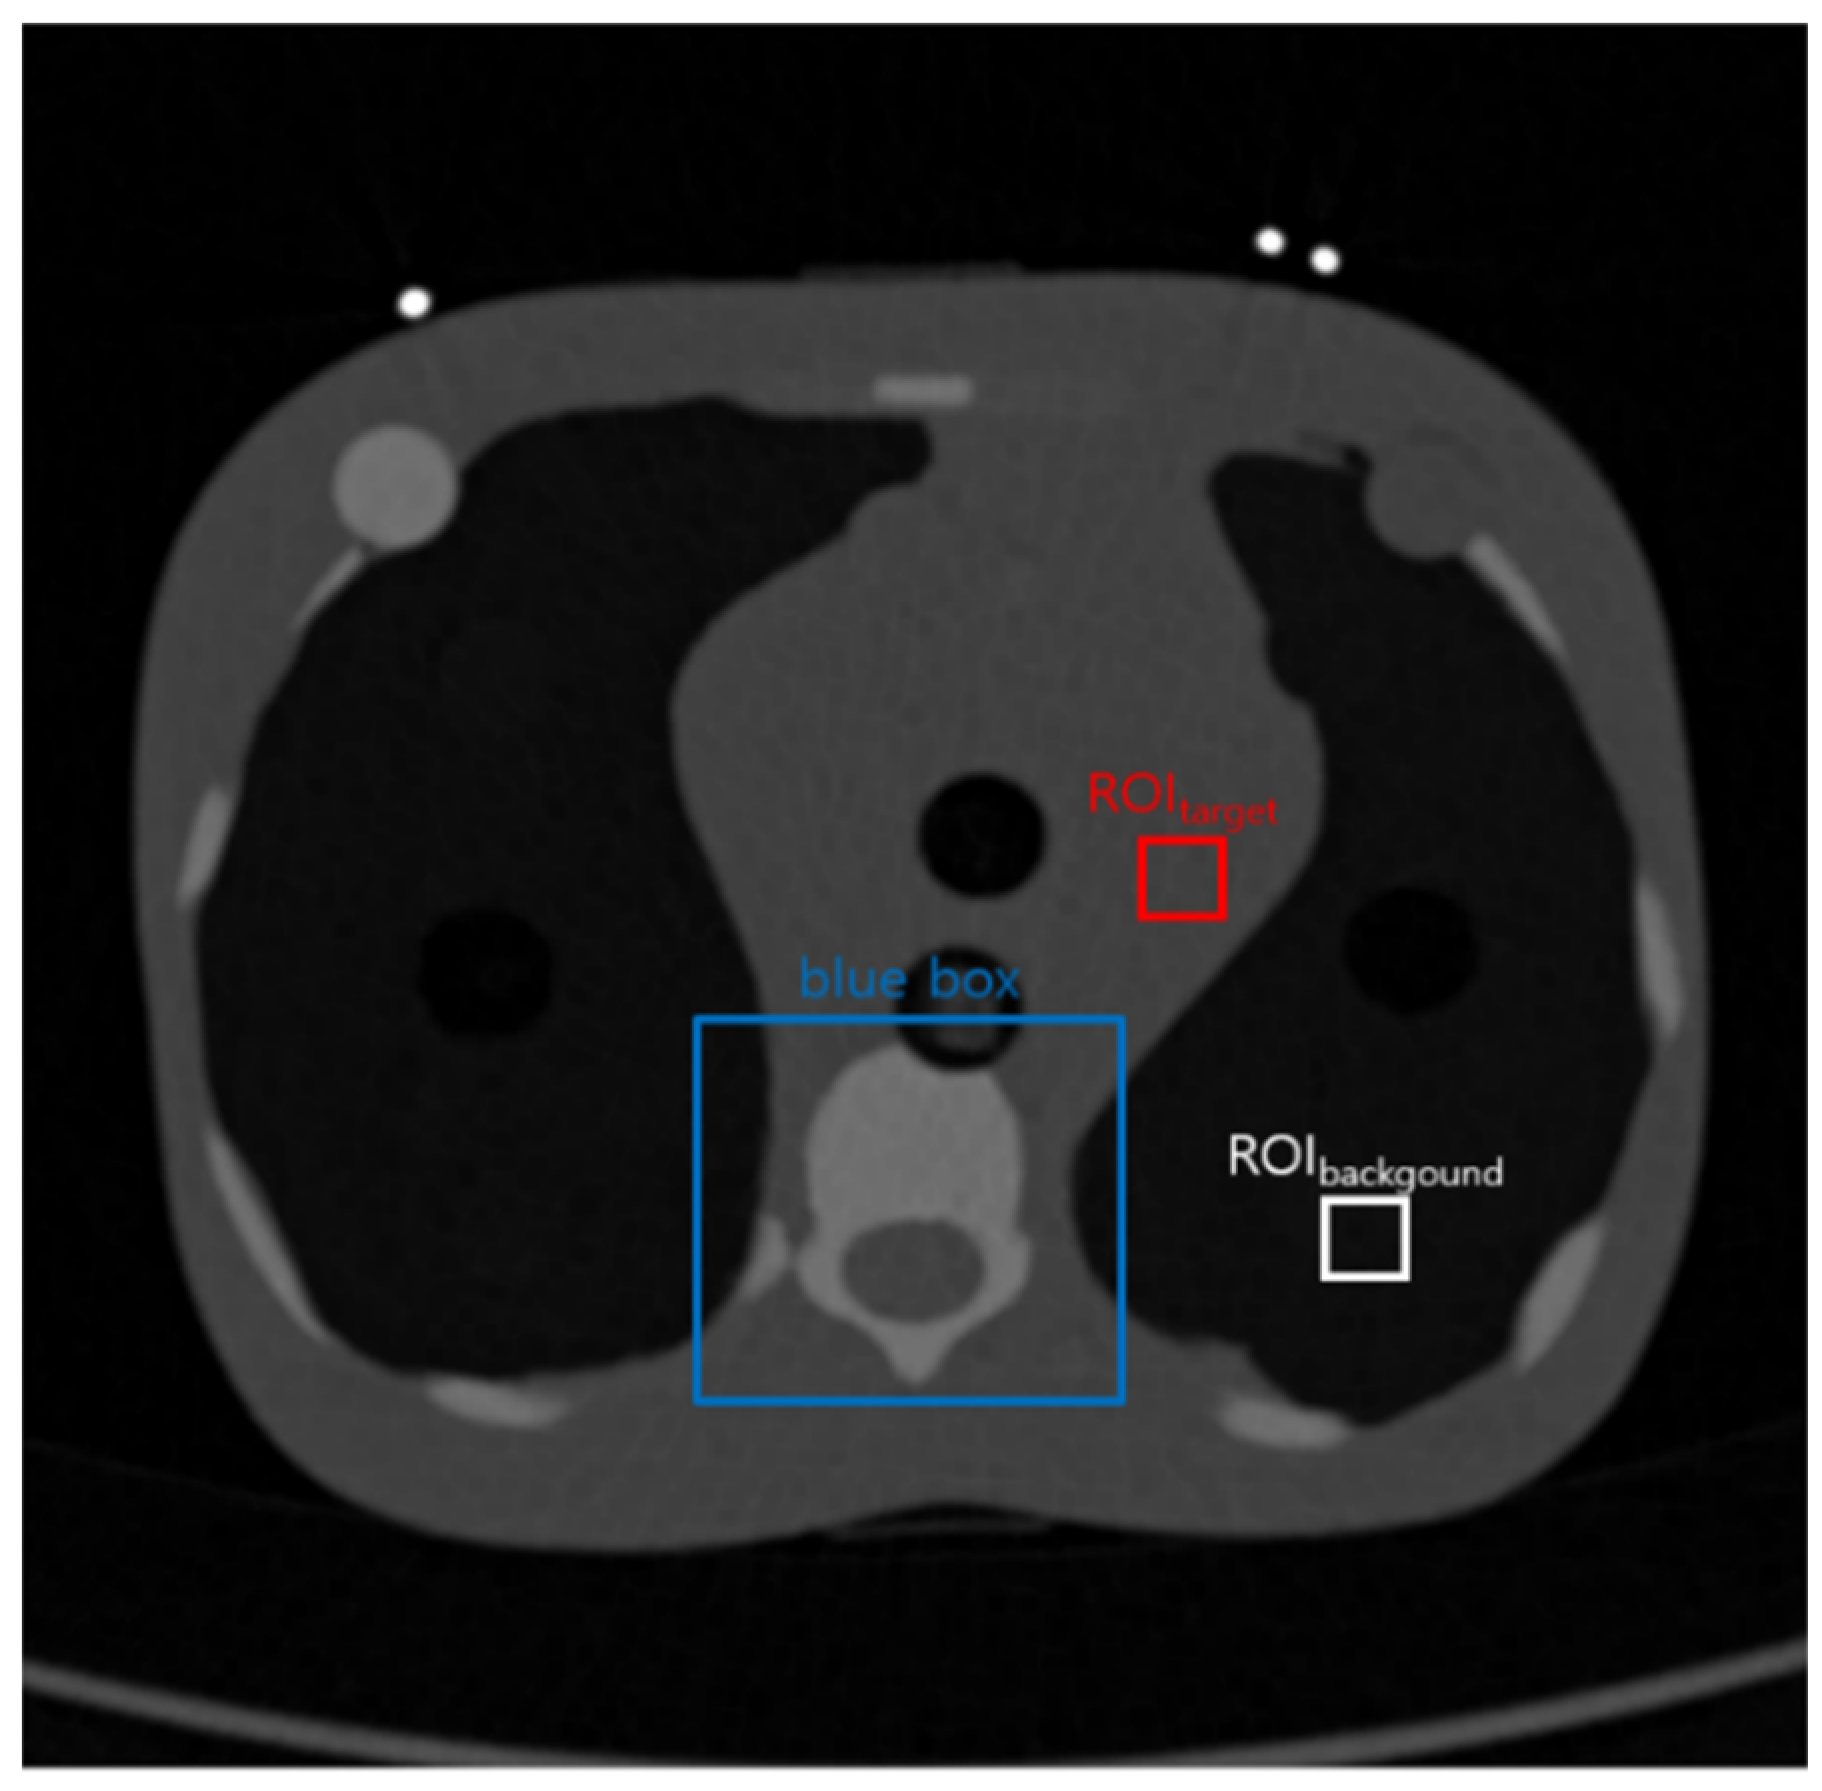

2.2. Acquisition of the Thoracic Image from the Five-Year-Old Phantom: The Practical Study

2.4. Quantitative Evaluation Factors

2.4.1. Evaluation Factors for the Noise Level